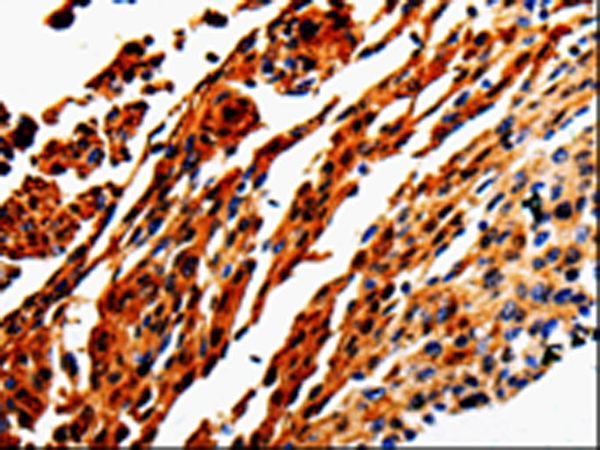

分类: 科研抗体货号: P06971别名: FETA, HPAFP应用: WB,IHC反应种属: Human